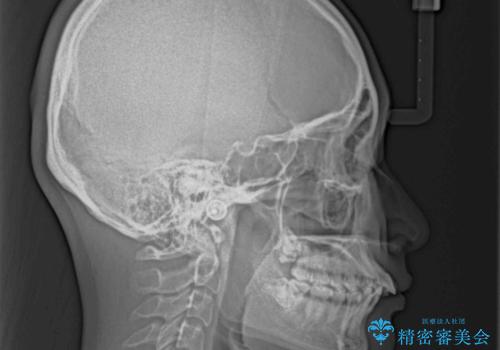

- 下顎の前歯が上顎の歯肉に咬みこむくらいに突出した上顎前歯を気にして来院された患者様です。

口元の突出感はないものの、上顎前歯が前方に傾斜して突出しており、前後に大きなズレがあり非常に深い咬み合わせとなっていました。

前突間を改善するため、上顎左右の第一小臼歯を抜歯してワイヤー装置にて矯正治療を行うこととしました。